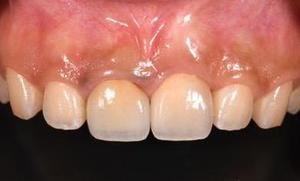

前歯審美症例

上顎前歯1本欠損症例

BEFOREAFTER69歳男性/上1本/インプラント埋込手術 【治療内容】 右上前歯の歯根が破折し、抜歯と...